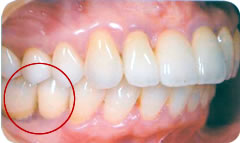

歯を製作するためにお口の中の型を取ります。製作した人工歯をアバットメント(支台部)に装着して完成です。